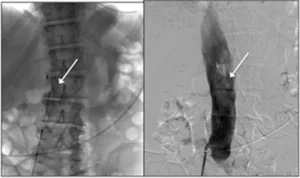

3. Filtro Cavale

Un filtro cavale è un dispositivo che viene posizionato nella vena cava inferiore per impedire la migrazione dei trombi verso i polmoni, riducendo il rischio di embolia polmonare. Questo dispositivo è posizionato dal radiologo interventista sotto guida radiologica, con accesso dalla vena femorale comune (inguine), dalla vena giugulare interna (collo) o dalla vena brachiale (braccio).

Il filtro cavale è rimovibile e può essere rimosso in seguito, quando il rischio di migrazione dei trombi è stato risolto (ad esempio, una volta che la trombosi venosa profonda è guarita). La rimozione avviene sempre sotto guida radiologica, con un approccio minimamente invasivo.

Posizionamento di filtro cavale (freccia bianca) con approccio femorale